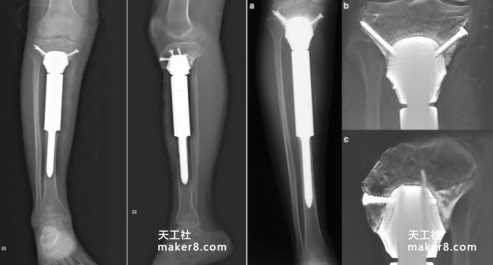

26个月后随访

在接受手术后,该青少年似乎对3D打印假体植入物的耐受度很好。26个月后对该男孩进行随访,其表现出“令人满意的肢体功能”,能够行走、奔跑、跳跃且不会感到疼痛。该假体与真正的胫骨吻合良好,膝关节展现出0-130°的运动并且Enneking功能评分为93%,这与正常膝关节相比是具有“可比性”的。